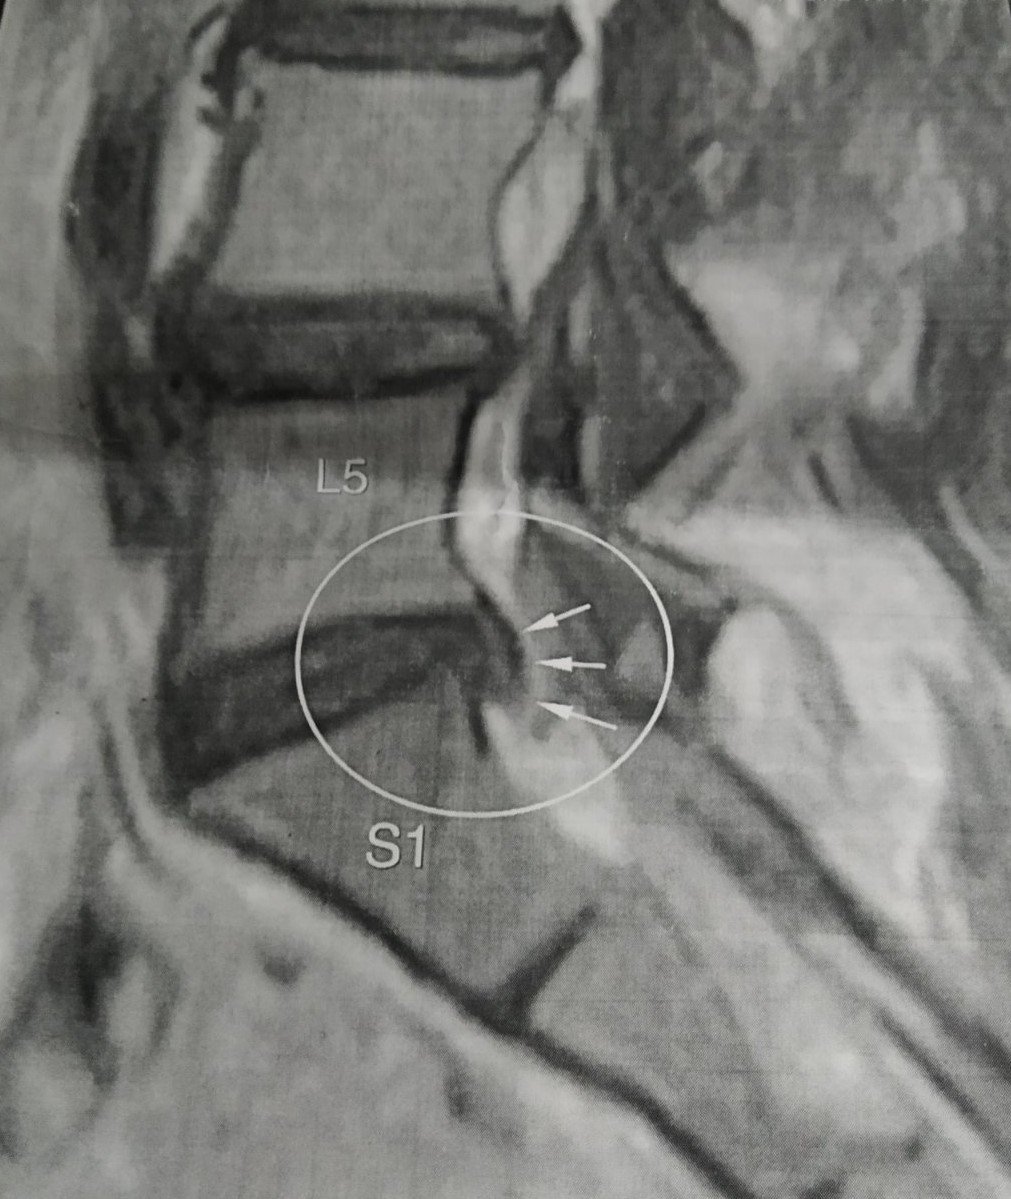

Всередині хребта є порожнина, в якій знаходиться центральна нервова система — спинний мозок. Внаслідок цих хвороб — остеохондроза, спонділоартроза , спондильоза- виникають грижі, протрузії. Це призводить до того, що простір між хребцями звужується. Для повноцінного фукціювання мозку потрібна глюкоза. 90% глюкози із нашого організму потребує головний мозок. Глюкоза в головний мозок поставляється ліквоїдною або цереброспинальною рідиною, яка циркулює в порожнині спинного мозку і яка рухається по хребту під час руху.

Спондилоартроз — патологічні зміни і руйнування міжхребцевих суглобів, які спричиняють порушення їх функції, і як наслідок – виникають сильні больові відчуття. Спондилоартроз мають 80-90% людей похилого віку. Бо більшість людей мало приділяють часу для профілактики захворювань хребта. В першу чергу хвороба вражає міжхребцеві диски (остеохондроз) — зниження їх висоти внаслідок їх перевантаження.